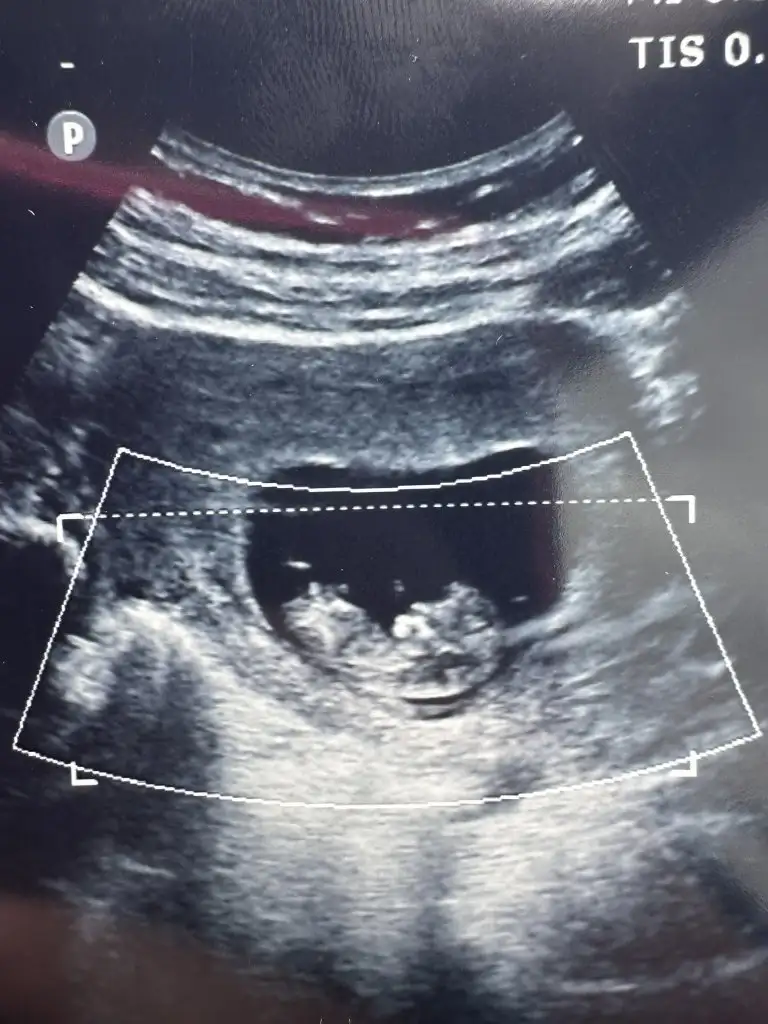

Merhaba ben kadın doğumda ikili taramaya girdim.Kendi kadın doğum doktorum söyledi cinsiyet tahminini detaylı ultrasondaBizde şimdi ikili tarama için geldik hayırlısıyla güzel sonuçlarla atlatırız inşallah cinsiyet tahminini kim söyledi acaba?ikili tarama için radyolojiden randevu aldık biz ondan soruyorum

Bende haftaya cuma tekrar gidiyorum ikili test için 45 mm olması lazımmış benim 39 mm dediCinsiyetler belli olmaya başlamışçatlıyorum ya daha haftaya perşembe gideriz biz ikili için of

Maşallah bı şey dicem ikili testi yapmak için aç mi tok mu gittiniz kan falan verildi miBenimde dun ikili testim yapildi iki ayri doktorda randevumvardi ikiside erkek dedi12. Haftamdayım